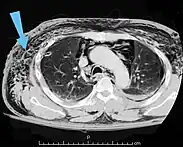

| An abdominal CT scan of a patient with subcutaneous emphysema (arrows) | |

Significant cases of subcutaneous emphysema are easy to diagnose because of the characteristic signs of the condition.[1] In some cases, the signs are subtle, making diagnosis more difficult.[13] Medical imaging is used to diagnose the condition or confirm a diagnosis made using clinical signs. On a chest radiograph, subcutaneous emphysema may be seen as radiolucent striations in the pattern expected from the pectoralis major muscle group. Air in the subcutaneous tissues may interfere with radiography of the chest, potentially obscuring serious conditions such as pneumothorax.[18] It can also reduce the effectiveness of chest ultrasound.[27] On the other hand, since subcutaneous emphysema may become apparent in chest X-rays before a pneumothorax does, its presence may be used to infer that of the latter injury.[13] Subcutaneous emphysema can also be seen in CT scans, with the air pockets appearing as dark areas. CT scanning is so sensitive that it commonly makes it possible to find the exact spot from which air is entering the soft tissues.[13] In 1944, M.T. Macklin and C.C. Macklin published further insights into the pathophysiology of spontaneous Macklin's Syndrome occurring as a result of a severe asthmatic attack.